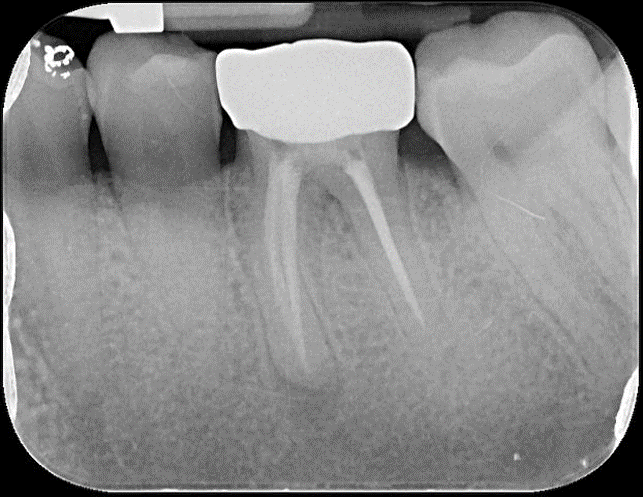

治療前,根管治療後